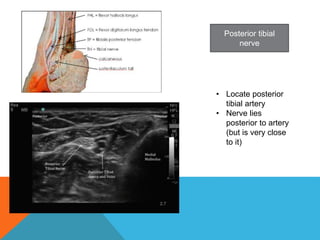

Posterior tibial

nerve

• Locate posterior

tibial artery

• Nerve lies

posterior to artery

(but is very close

to it)

Posterior tibial nerve • Locateposterior tibial artery • Nerve lies posterior to artery (but is very close to it)